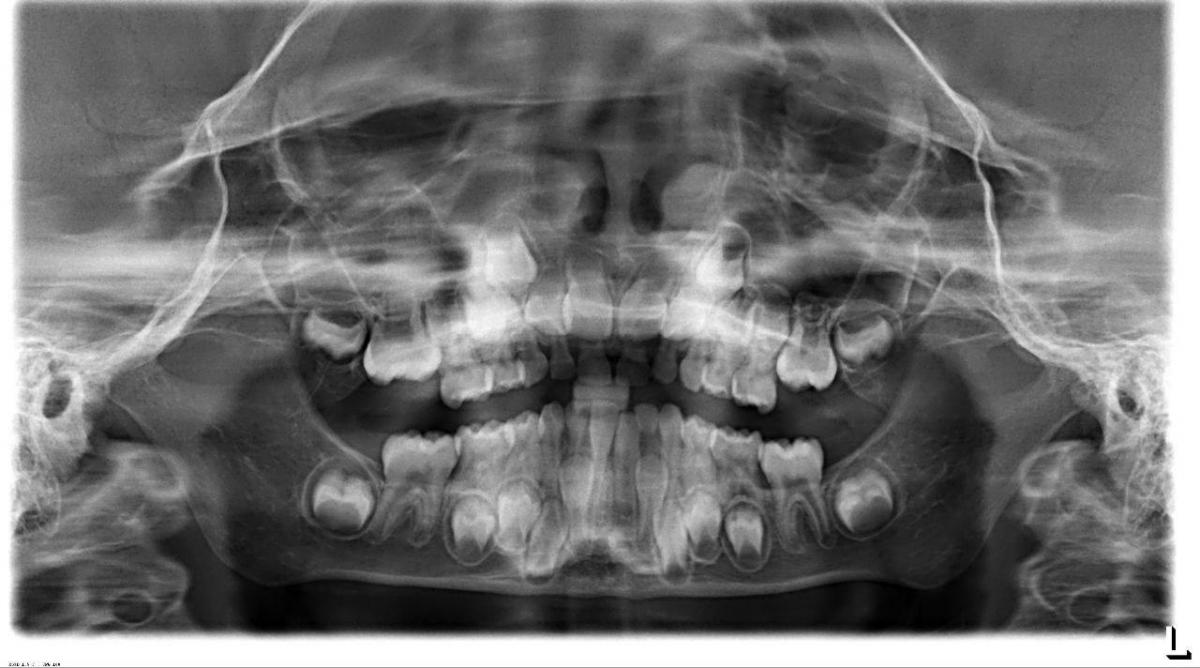

Стоматологические Исследования: Рентген Инвагинации Зубов